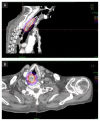

Brachytherapy (BT) is an important local treatment of tumor and it can be applied to different anatomical sites either in a curative or palliative setting. BT can deliver large dose of radiation to the tumor while sparing the surrounding normal tissue which translates into a better therapeutic ratio compared to external beam radiotherapy. However, the evidence for the use of brachytherapy in the palliative setting is lacking in the literature. In this case report, we describe the brachytherapy technique and outcome of a patient with squamous cell carcinoma of the hypopharynx who underwent palliative brachytherapy to the hypopharynx and metastatic tumor at the right axilla.